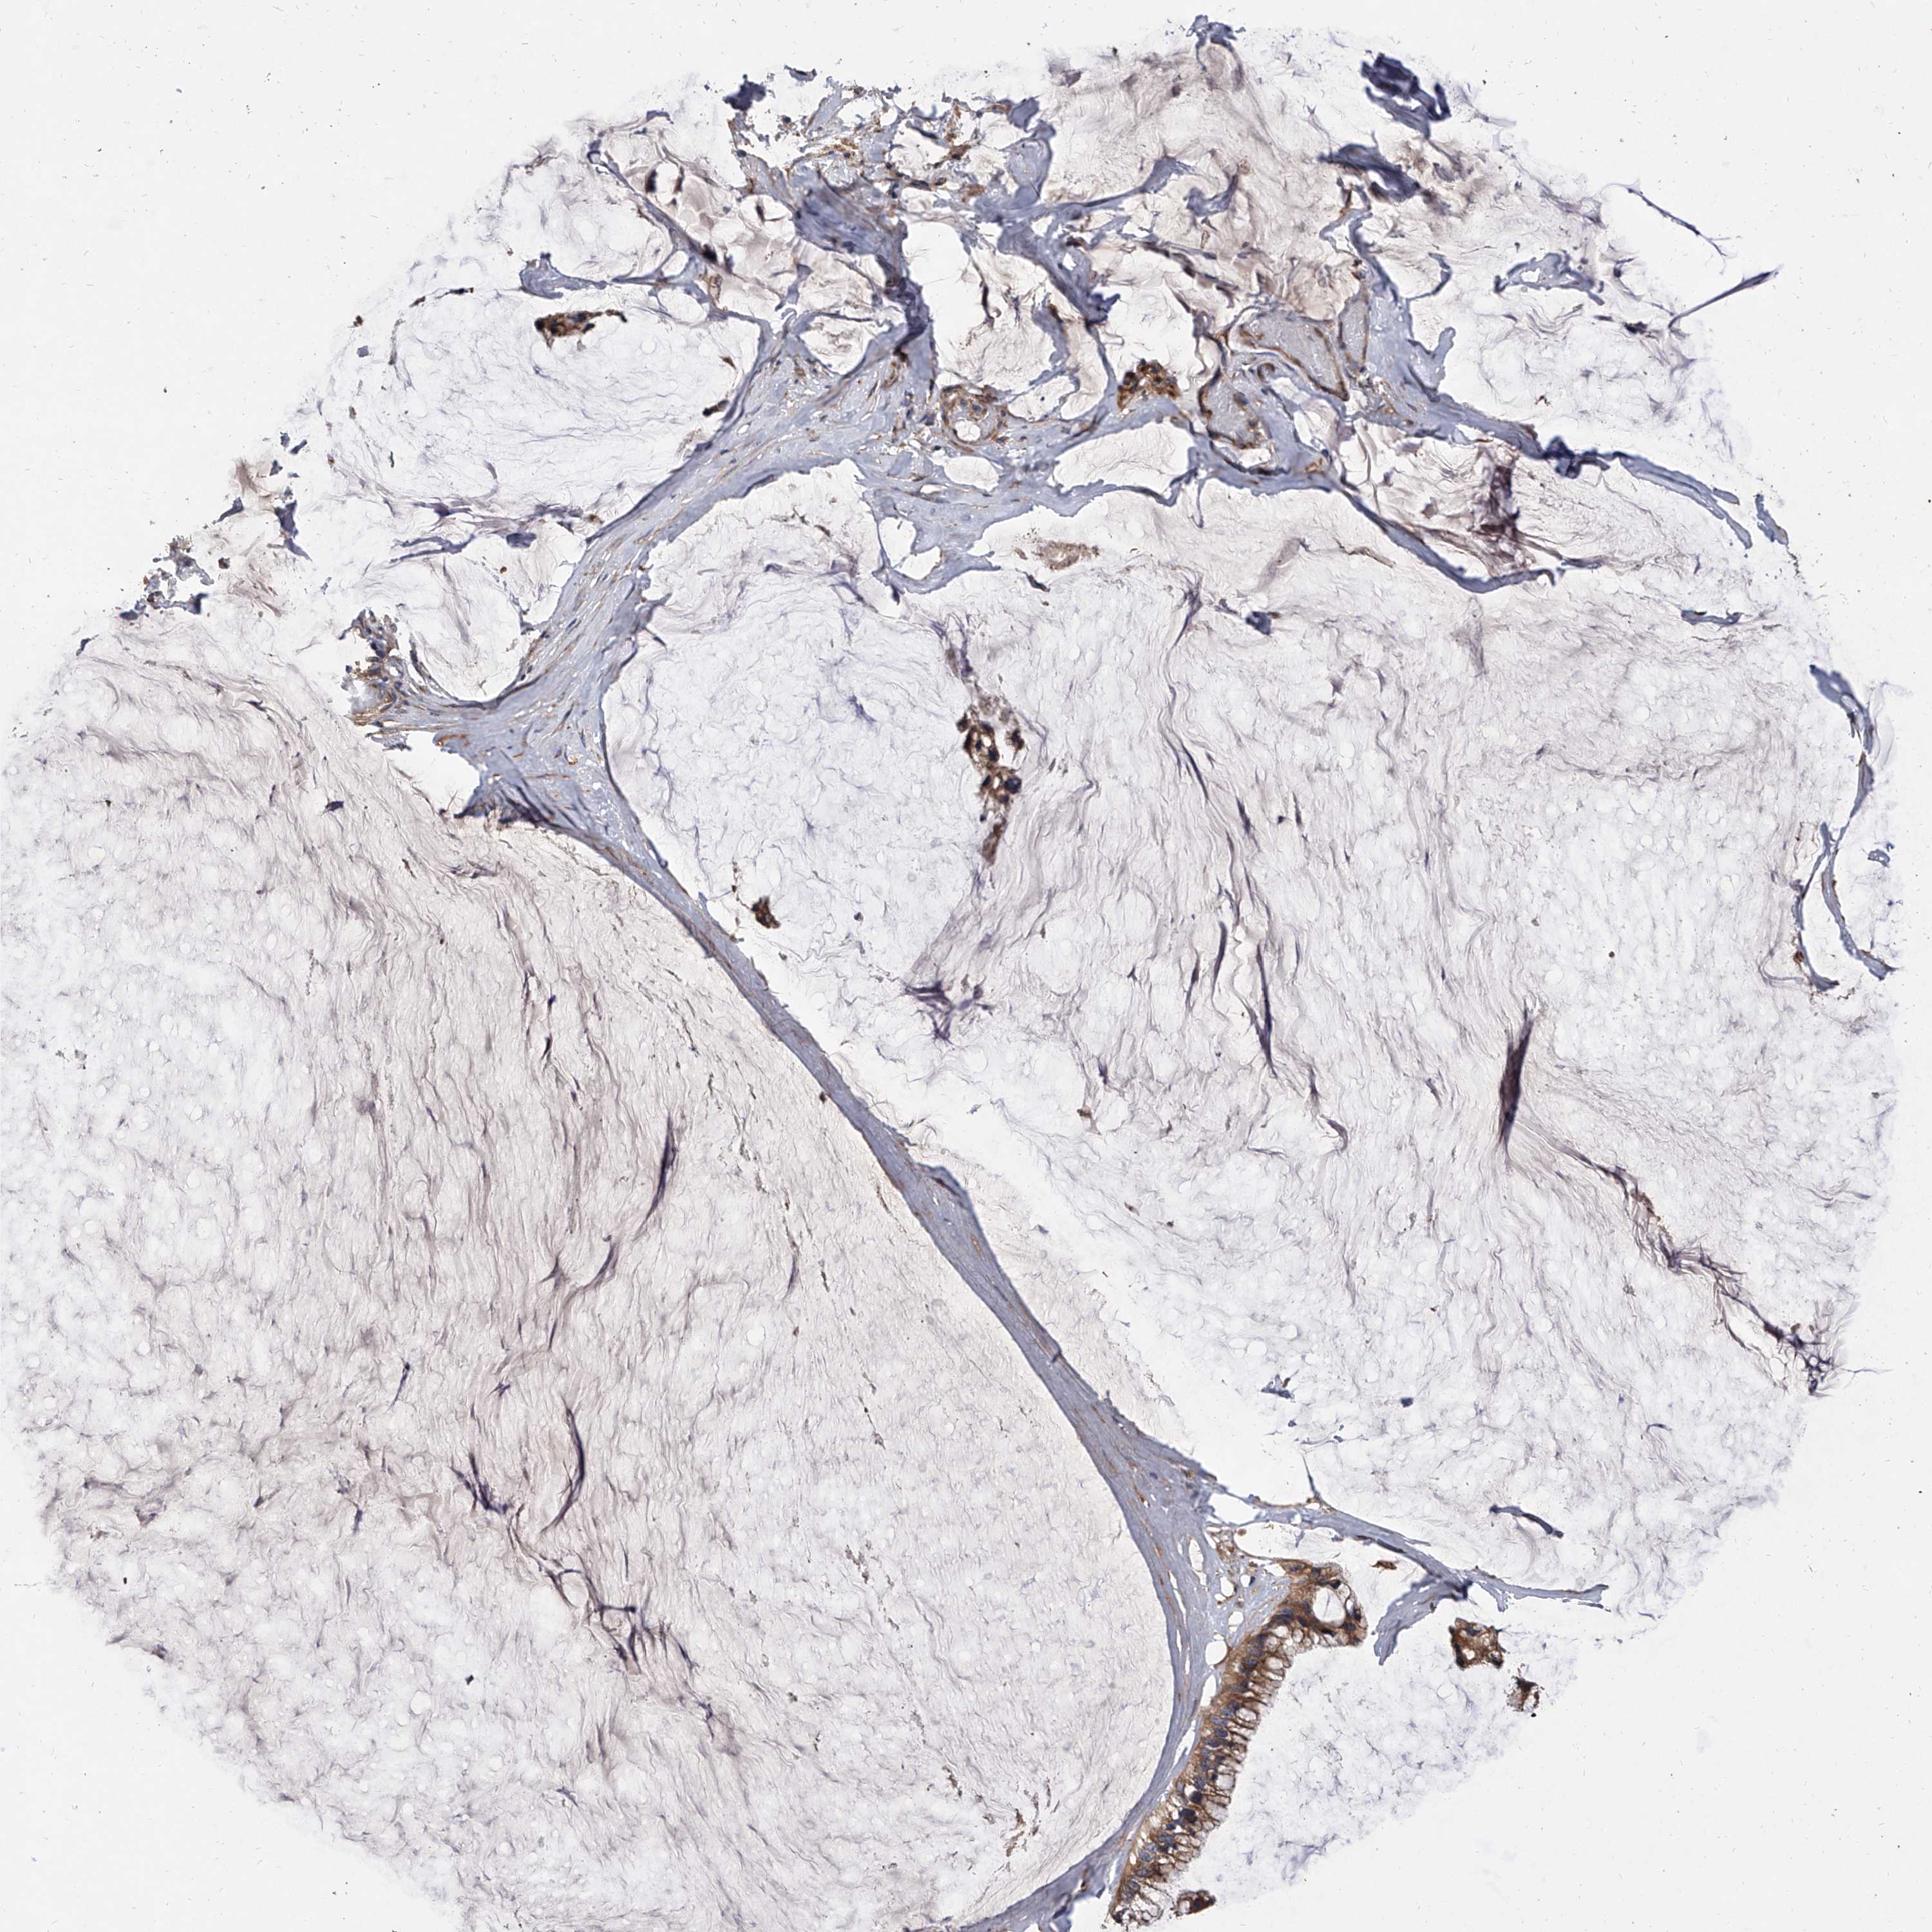

OVARIAN CANCER - Protein expressioni

A mouse-over function shows sample information and annotation data. Click on an image to view it in a full screen mode. Samples can be filtered based on level of antibody staining by selecting one or several of the following categories: high, medium, low and not detected. The assay and annotation is described here.

Note that samples used for immunohistochemistry by the Human Protein Atlas do not correspond to samples in the TCGA dataset.

Antibody stainingi

Antibody staining in the annotated cell types in the current human tissue is reported as not detected, low, medium, or high, based on conventional immunohistochemistry profiling in selected tissues. This score is based on the combination of the staining intensity and fraction of stained cells.

Each image is clickable and will lead to virtual microscopy that enables deeper exploration of all samples and also displays staining intensity scores, fraction scores and subcellular localization as well as patient and tissue information for each sample.

Antibody HPA031443

Staining

High

Medium

Low

Not detected

Intensity

Strong

Moderate

Weak

Negative

Quantity

>75%

75%-25%

<25%

None

Location

Nuclear

Cytoplasmic/membranous

Cytoplasmic/membranous,nuclear

Cystadenocarcinoma, serous, NOS

Carcinoma, endometroid

Cystadenocarcinoma, mucinous, NOS

Carcinoma, NOS